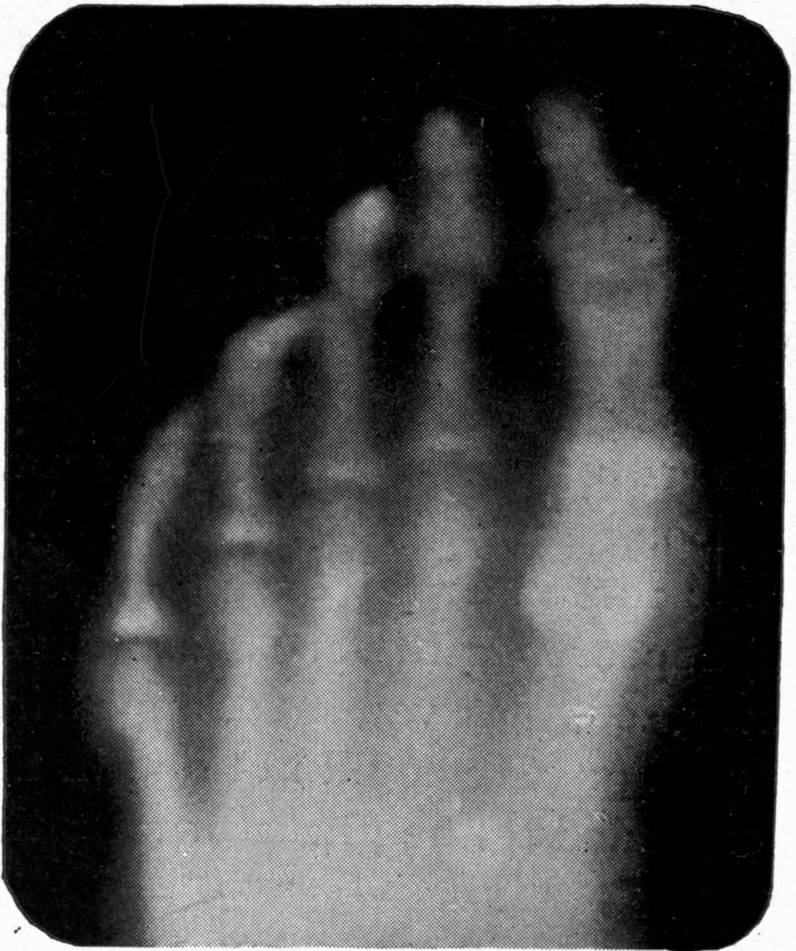

Fig. 4.—Knee, Knickerbocker Buttons, Bullet in Femur.

FROM SCIAGRAPHS BY PROF. DAYTON C. MILLER. § 204.

117. Transposition of Phosphorescent Spot and of Cathode Rays without a Magnet. Salvioni, Elster, Geitel, and Tesla